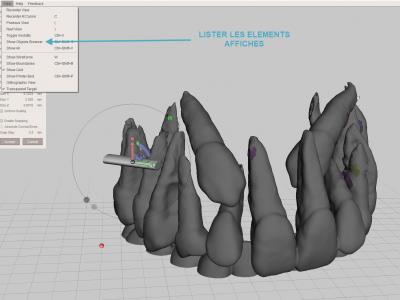

Avec le logiciel gratuit Meshmixer

- Importer le fichier STL

- Etape de nettoyage : il s'agit d'enlever tous les fragments osseux ou les zones non désirées. C'est l'étape la plus longue ! (Il faut penser à sauvegarder régulièrement pour éviter des accidents).

Différents séquences d'outils vont être utiles :

Sélectionner la surface de zone à éliminer avec l'outil "Select" "Brush", puis les supprimer avec le raccourci clavier "X"

Sélectionner une zone complète à éliminer avec l'outil "Select" "Lasso", puis les supprimer avec le raccourci clavier "X"

Pour éliminer les fragments non reliés : sélectionner une ou plusieurs petites zones à garder (dents par exemple) avec l'outil "Select" "Brush", puis opération "Expand to connected", puis inversion de la sélection avec la touche "I", puis les supprimer avec le raccourci clavier "X"